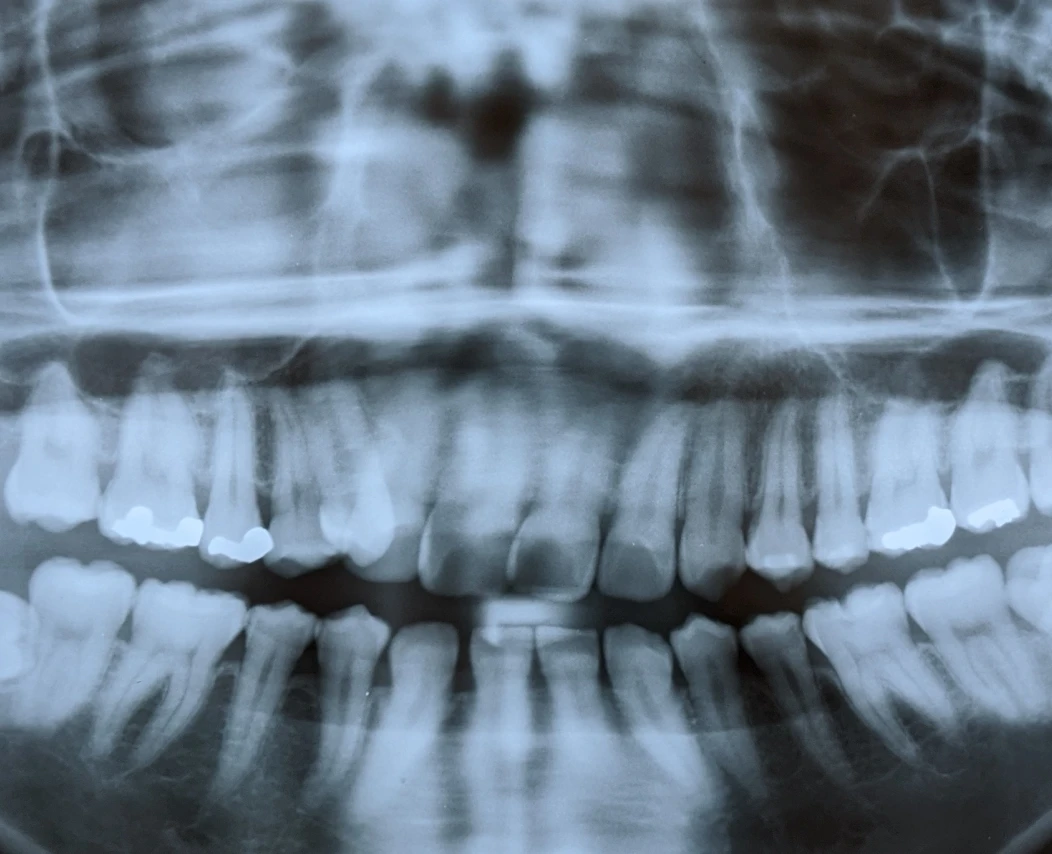

歯周病とは、歯を支える歯周組織が少しずつ破壊されていく病気です。

日本では歯を失う原因の第1位とされており、30歳以上の約半数が歯周病にかかっていると言われています。

近年では発症の若年化も進み、10代・20代でも決して珍しい病気ではありません。

歯周病は初期の段階ではほとんど自覚症状がなく、気づいたときには症状が進行しているケースが多いのが特徴です。

しかし、早期に発見し適切なケアを行うことで、進行を抑え、大切な歯を守ることができます。